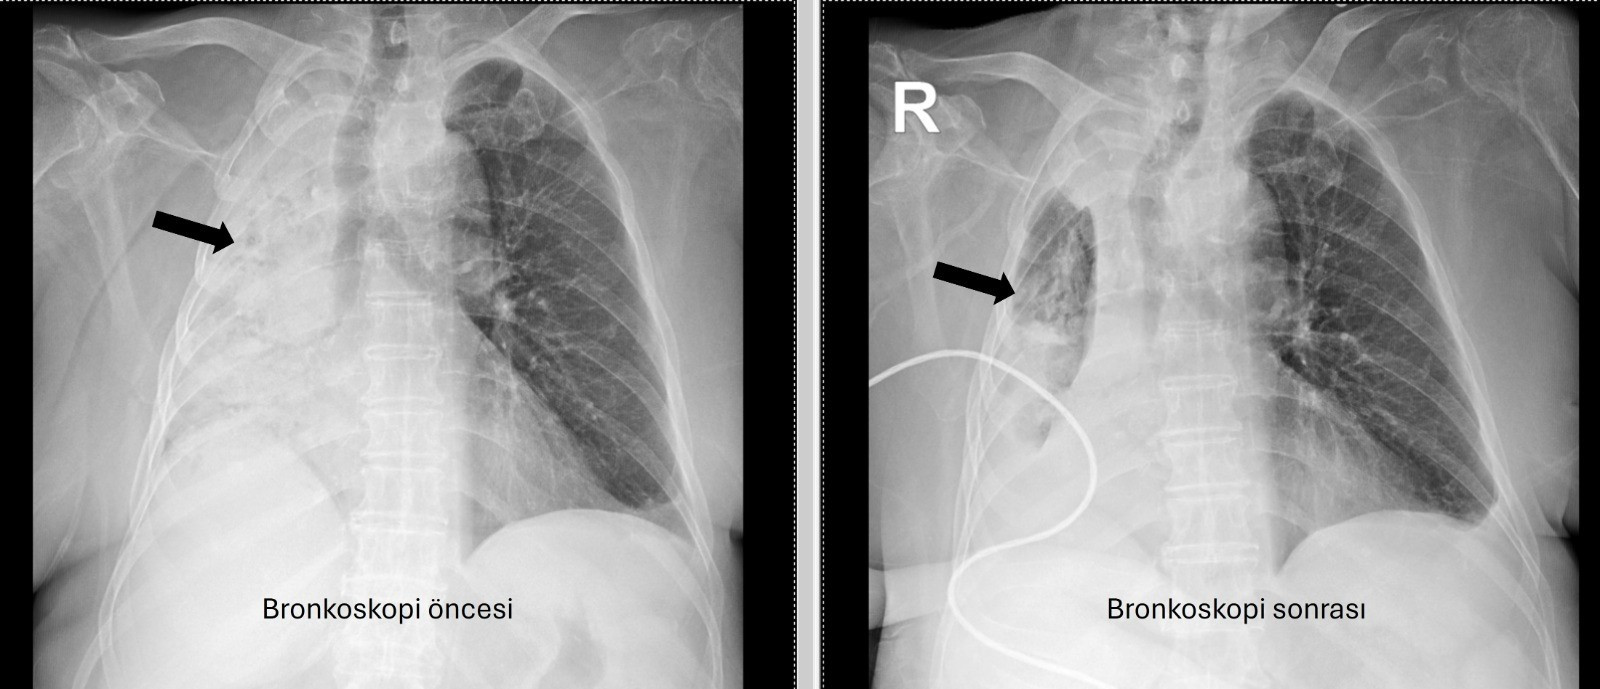

Son başvurduğu hastanede sağ akciğerinin tamamen kapalı olduğu saptanınca, hasta Pamukkale Üniversitesi Hastanesi’ne yönlendirildi. PAÜ Göğüs Hastalıkları Anabilim Dalı’ndan Prof. Dr. Göksel Altınışık Ergur, yapılan tetkiklerde sağ akciğere giden hava yolunun tamamen tıkalı olduğunu belirledi.

Prof. Dr. Altınışık Ergur, hastaya acil bronkoskopi planlandığını ve işlemin hemen yapıldığını belirtti: “Esnek bronkoskop ile hava yolları incelendiğinde yoğun, koyu sekresyonlar görüldü; temizlik sonrası inceleme mümkün oldu. Aspiratörle steril sıvı verilerek temizlik yapıldı ve sağ akciğere giden hava yolunda sarı bir cisim fark edildi. Bunun yabancı cisim olduğu ve mısır tanesine benzediği anlaşıldı. Yabancı cismi çıkarmak için genel anestezi altında rijit bronkoskop planlanabilirdi; çünkü tedavi, cismin sorunsuz çıkarılmasıydı.

Ancak hastanın genel durumu, ek hastalıkları ve enfeksiyonu nedeniyle genel anestezi riskliydi. Bu yüzden cismin fark edildiği anda çıkarılmasına karar verildi. Aspiratörün emme gücüyle cisim çıkarılabilirdi. Bronkoskopun ucu cismin gövdesine dayandırılıp aspiratörle emilerek sıkıca yapıştırıldı. Emme gücü sabit tutularak cisim ve bronkoskop hava yollarından başarıyla çıkarıldı. İşlem sonrası hasta yakınına mısır tanesiyle ilgili öykü sorulduğunda, beş ay önce hastanın mısır taneli pizza yediği öğrenildi. O an belirti oluşmaması nedeniyle bu durum düşünülmemişti. Düşkün hastalarda taneli gıdaların fark edilmeden bu sorunu yaratabileceği, hastaların dedektif titizliğiyle değerlendirilmesi gerektiğini gösteriyor.” dedi.